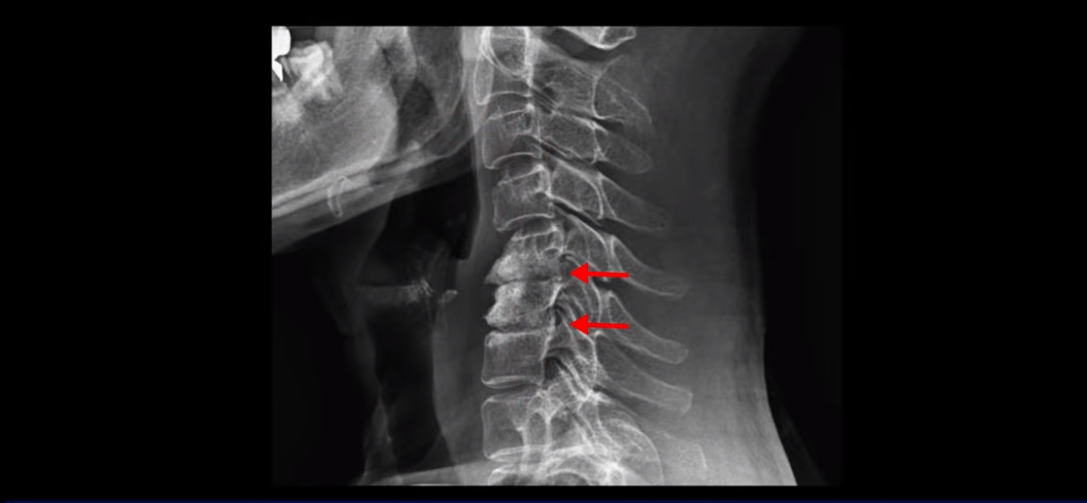

그래서 오른쪽 신경 가지가 빠져 나가는 추간공 2개와

왼쪽 추간공 두 개가 모두 많이 좁아져 있습니다.

이렇게 신경 구멍들이 좁아져 있고 신경 주사가 효과가 없으니까 동네 정형외과에서는 무조건 대학병원으로 가라고 했는데요. 가서 수술 받으라는 얘기겠죠. 그런데 저희 모커리한방병원은 협착증은 수술 없이 치료가 잘 될 수 있는 질환이라고 계속 설명하고 있는데요. 왜 그럴까요? 저희가 협착증이 왜 수술 없이 치료 가능하다고 설명하는지에 대해 잘 이해하시려면 무증상 협착이라는 개념에 대해 잘 이해하셔야 합니다.